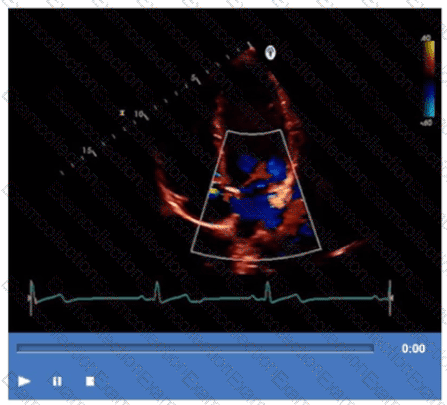

Which type of valvular lesion most commonly requires further evaluation with a non-imaging transducer?